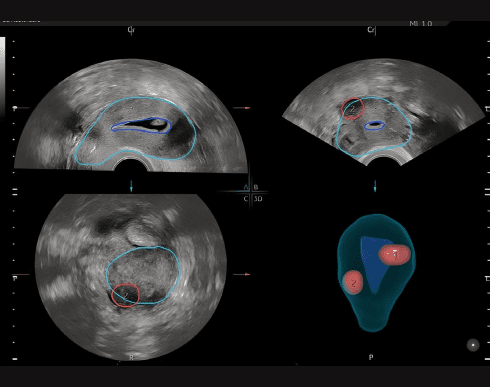

Функція SonoGYN

Комбінує наш інструмент Uterine Trace та функцію Fibroid Mapping для створення звітів за допомогою штучного інтелекту, з картуванням міоми в 3D.